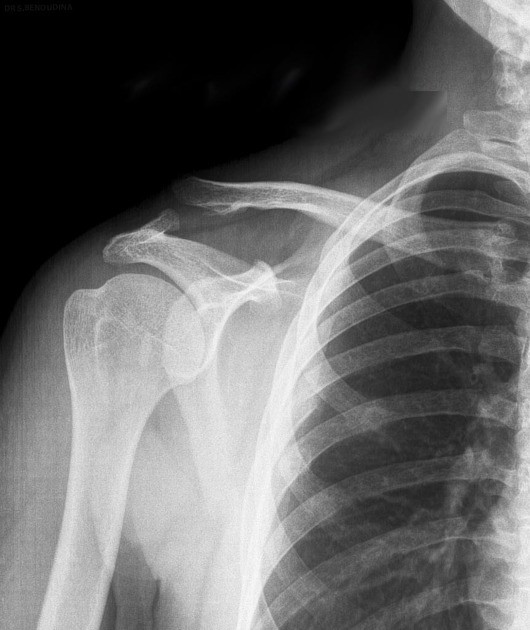

Imaging

- X-rays to confirm alignment

- Stress X-rays (holding a weight) if needed

The diagnosis is usually straightforward when deformity is present.